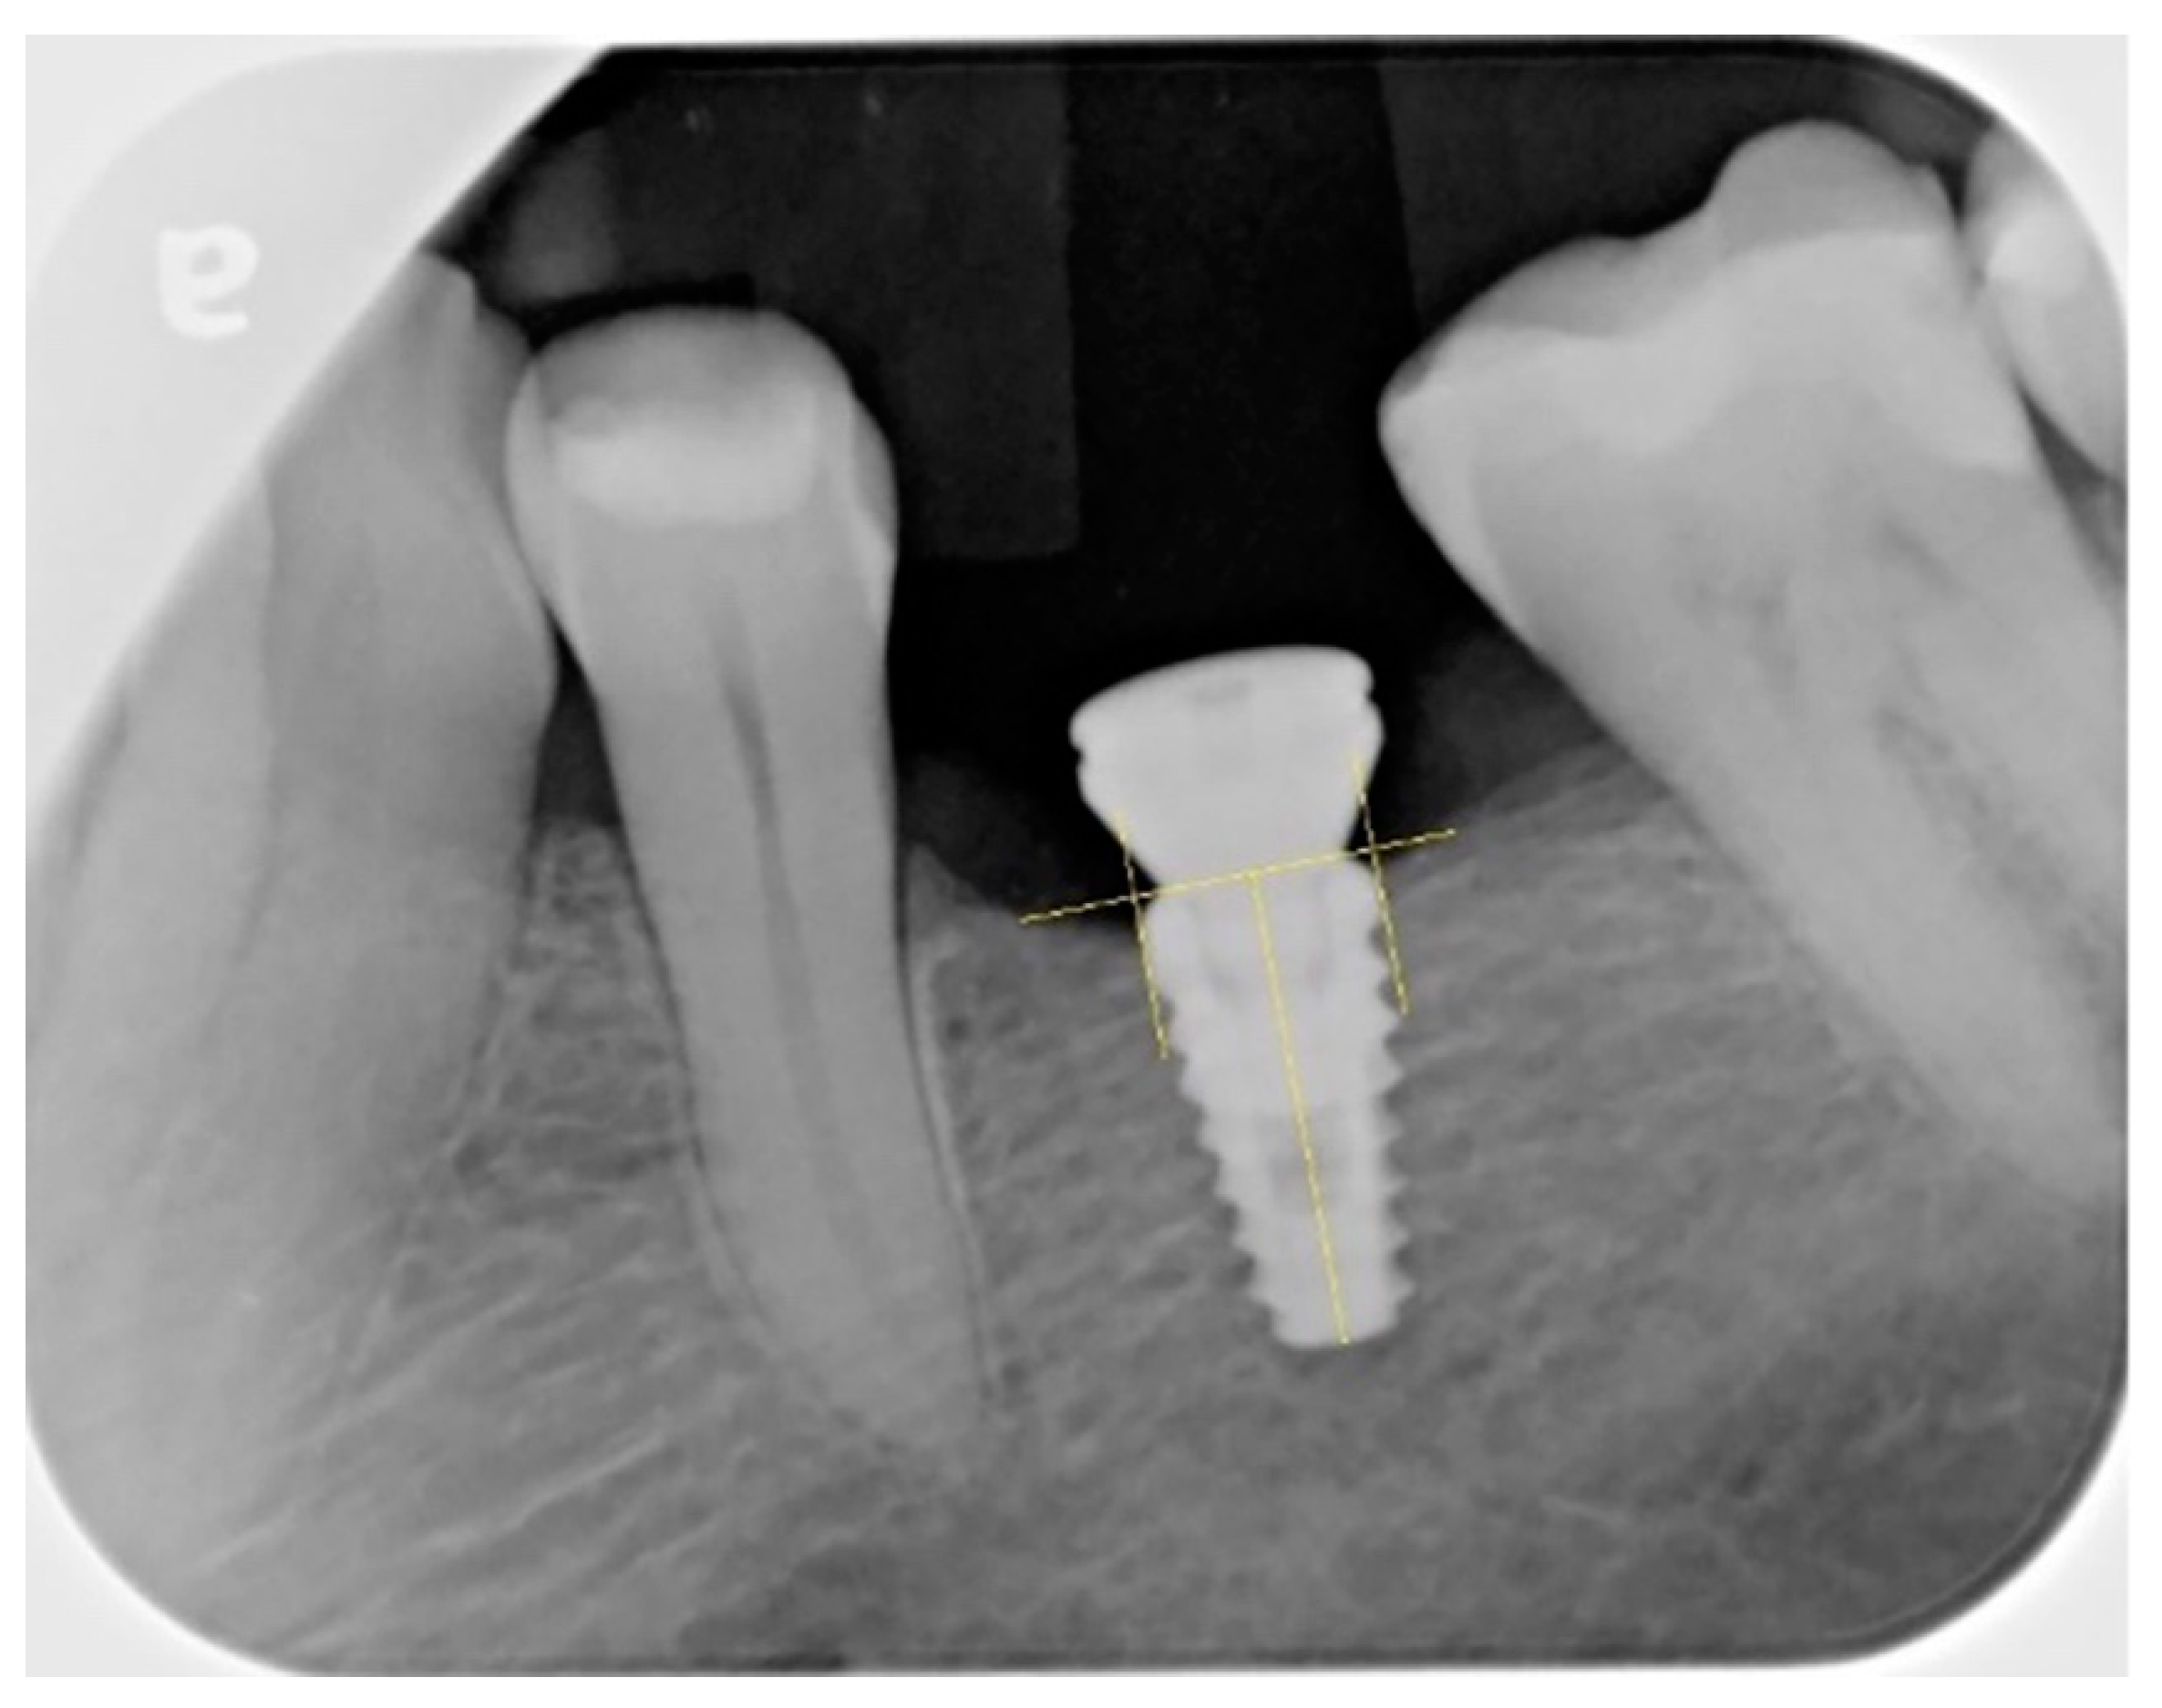

2.5. Radiographic Measurements

- Cosola, S.; Toti, P.; Peñarrocha-Diago, M.; Covani, U.; Brevi, B.C.; Peñarrocha-Oltra, D. Standardization of three-dimensional pose of cylindrical implants from intraoral radiographs: A preliminary study. BMC Oral Health 2021, 21, 100. [Google Scholar] [CrossRef] [PubMed]